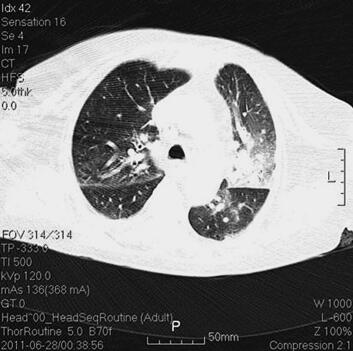

体格检查:P 85次/分,R 12次/分(机械通气),BP 121/61mmHg(多巴胺针剂维持下),T 37.3℃,SPO2 98%。神志清,精神差,气管居中,口插管在位,机械通气,颈静脉无怒张,桶状胸,两肺呼吸音粗,可闻及大量湿啰音及干啰音,心率85次/分,窦性,律齐,双下肢无明显水肿。辅助检查:胸部CT(6月28日)(图1):两肺感染性病变,两下肺支气管扩张症伴感染。心电图(6月28日):窦性心律,T波改变。血常规(6月28日):WBC 13.5×109/L,N 66.3%,Hb 145g/L;CRP(6月28日)3.8mg/L,PCT(6月28日)5.49ng/ml。

图1 胸部CT(6月28日):两肺感染性病变,两下肺支气管扩张症伴感染